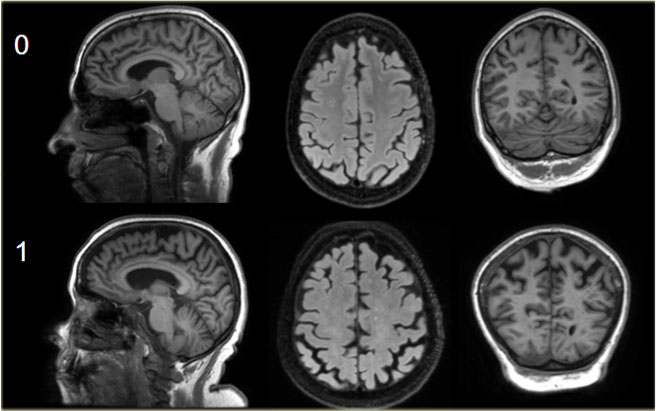

Koedam score for Parietal Atrophy

In addition to medial temporal lobe atrophy, parietal atrophy also has a positive predictive value in the diagnosis of AD.

Atrophy of the precuneus is particularly characteristic of AD (15).

This is particularly the case in young patients with AD (presenile AD), who may have normal MTA-scores.

The Koedam scale rates parietal atrophy - assessed in sagittal, coronal and axial planes.

In these planes, widening of the posterior cingulate and parieto-occipital sulci as well as parietal atrophy (including the precuneus) is rated (Table).

Koedam scale grade 0-1 Koedam scale grade 0-1

Koedam scale grade 0-1

Sagittal T1-, axial FLAIR- and coronal T1-weighted images illustrating the Koedam scale of posterior atrophy.

When different scores are obtained in different orientations, the highest score must be considered (16).

Koedam scale grade 2-3 Koedam scale grade 2-3

Koedam scale grade 2-3

The yellow arrows point to extreme widening of the posterior cingulate en parieto-occipital sulci in a patient with grade 3 posterior atrophy.